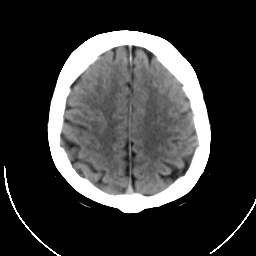

The x-ray CT scan was obtained about 3 hours after the

onset of symptoms and is normal. (Remember, these image datasets

have been spatially matched so that a direct comparison between

image types is possible.)

It is common for CT images to be negative during the acute period of

stroke.